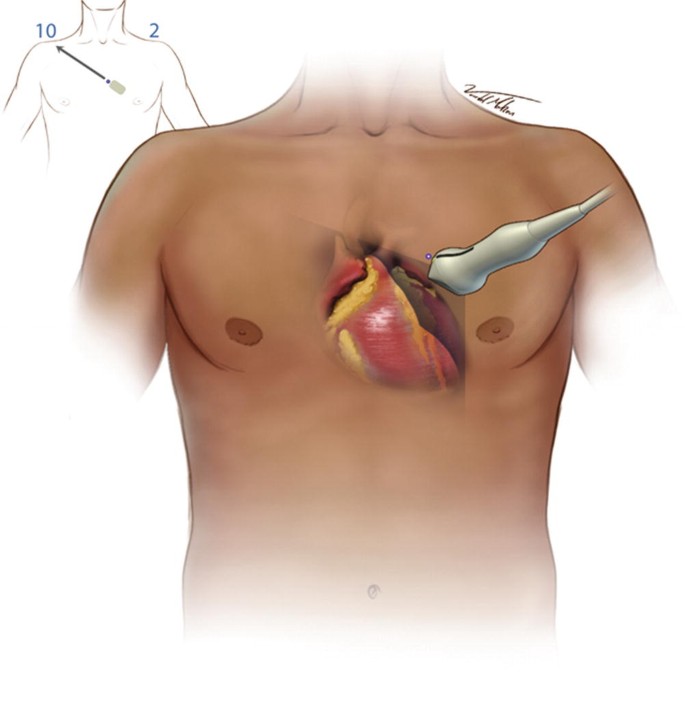

Where on the body is the LAX view performed?

Between the 3rd-5th intercostal space, where the transducer is close to the sternum, specifically the left sternal border.

In parasternal LAX, is the transducer close to the sternum or far?

Close.

Where should the orientation marker be pointing towards to obtain a parasternal LAX?

Towards the patient’s right shoulder. Image the heart inside the body.